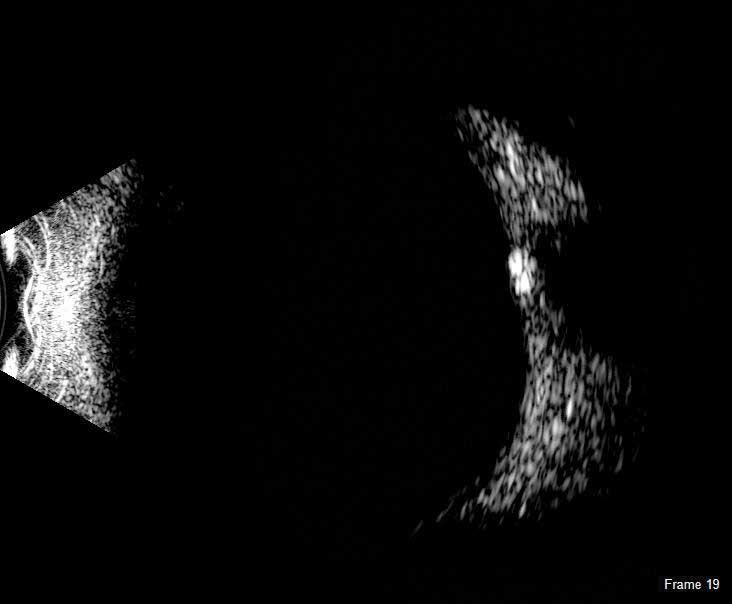

The redesigned B-Scan Probe, new with the Flex, provides clear imaging of the posterior segment of the eye, even when optical clarity is compromised.

TOTAL IMAGING SOLUTION

The Scanmate Flex B-Scan probe enables clinicians to capture clear and precise images and videos of the posterior segment of the eye. Ultrasonic B-scans are effective, even when opacities (such as dense cataract, blood, or anatomical structures) are present which obscure optical technologies.

The B-Scan probe is available in both 12.5 MHz and 20 MHz frequencies. Among the on-screen tools are calipers to measure structures, an area measurement tool and an annotation tool that gives you a way to indicate pathologies on the image.

B-Scan Diagnostic Applications

The Flex B-Scan delivers clear images of the posterior portion, even when optical clarity is compromised. B-Scan imaging can aid the evaluation of:

- Retinal Detachments

- Vitreous Detachments

- Vitreous Humor Pathologies

- Staphylomas

- Posterior Segment Pathologies

- Choroidal Pathologies

- Optic Nerve Pathologies

- Scleral Thickening